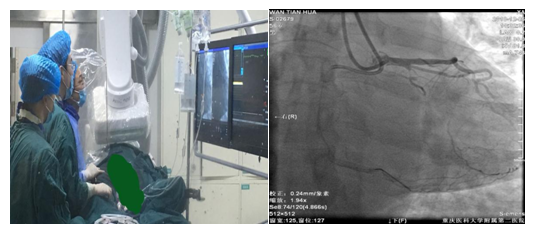

近日,我院心血管内科佘强教授团队利用IVUS指导,独立完成我院首例逆向开通高难度CTO 1例。患者为56岁男性, 1年前其在我科住院明确诊断为急性下壁心肌梗死,行冠状动脉造影显示回旋支CTO,右冠急性闭塞,行右冠PCI术。本次患者为开通回旋支再次入住我科。本次造影结果示回旋支开口后即完全闭塞,右冠状动脉支架通畅。患者本人及家属积极要求开通回旋支闭塞病变,术前佘强教授充分评估病变情况:其为回旋支病变,病变血管扭曲,闭塞入口不明,闭塞段大于20mm,并伴有钙化,J-CTO评分及PROGRESS CTO评分均达3分及以上,虽然存在良好侧枝,但以心外膜侧枝为主,且扭曲明显,可利用度较低,属于非常困难病变,经过充分准备,佘强教授制定正逆向的介入策略,在佘强教授指导下,由邓松柏博士主刀,刘亚杰博士等为助手完成该复杂病变手术。以双侧桡动脉为入路途径,术中克服了正向钙化、角度大、支撑力不足导致球囊、微导管、延长导管等不能进入病变,难以进行Reverse CART及AGT技术,逆向侧枝扭曲,逆向微导管难以通过及长度不够等诸多困难后,经抓捕、延长导丝、微导管对接等特殊技术,最终成功完成导丝体外化,后用血管内超声(IVUS)证实导丝全程在血管真腔,并经延长导管顺利植入支架1枚。经过6小时的持续努力,最终成功开通CTO血管。

随着逆向技术的掌握及应用,标志着我院冠脉介入技术又进入一个新的台阶。